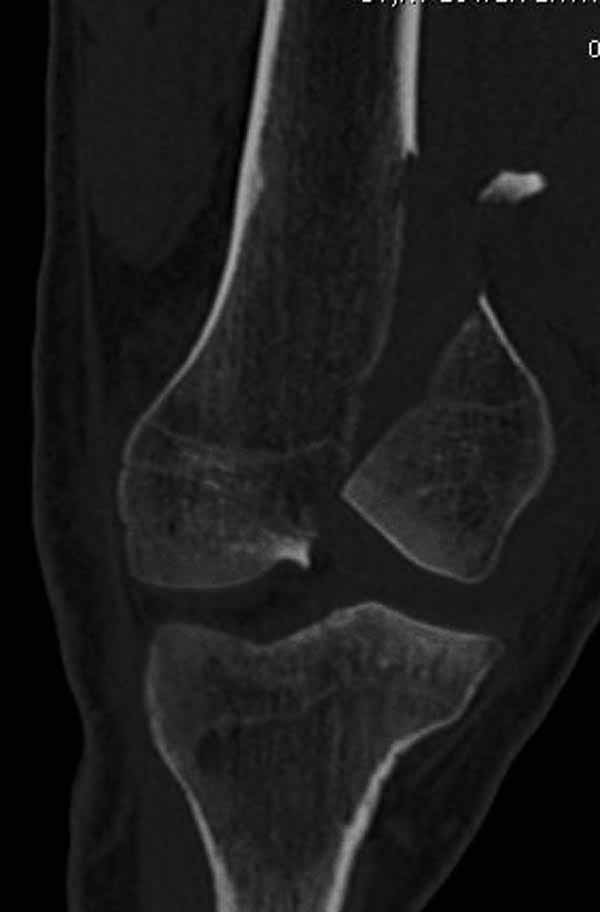

Остеосинтез, вестимо. КТ предварительно можно сделать, чтобы поточнее увидеть повреждения в межмыщелковой области. Перелом ближе к 33C1.

Представленный снимок не дает полную информацию. Там вроде простой перелом, но на самом деле, кроме смещенного (латерального, возможно медиального?) мыщелка на второй проекции имеется медиальный короткий дистальный фрагмент в флексии. Надо было сделать прямой снимок с захватом малоберцовой, который ориентировал бы стороны. Без КТ обычный снимок в дистракции поможет разобраться в топографии фрагментов.

И не обратите, коллега, пока не сделаете четкие анфасные снимки (лучше с дистракцией) где будет четко визуализироваться малоберцовая кость. Думается, что и КТ здесь будет уместно, дабы не пропустить возможное флексионное повреждение (перелом Hoffa).

А теперь по поводу лечения перелома. Среди всех чрез/меж-мыщелковых переломов в 38% сопровождются переломом в корональной плоскости, т.е перелом Hoffa. Nork et al, J Orthop Trauma, 87:564, 2005.